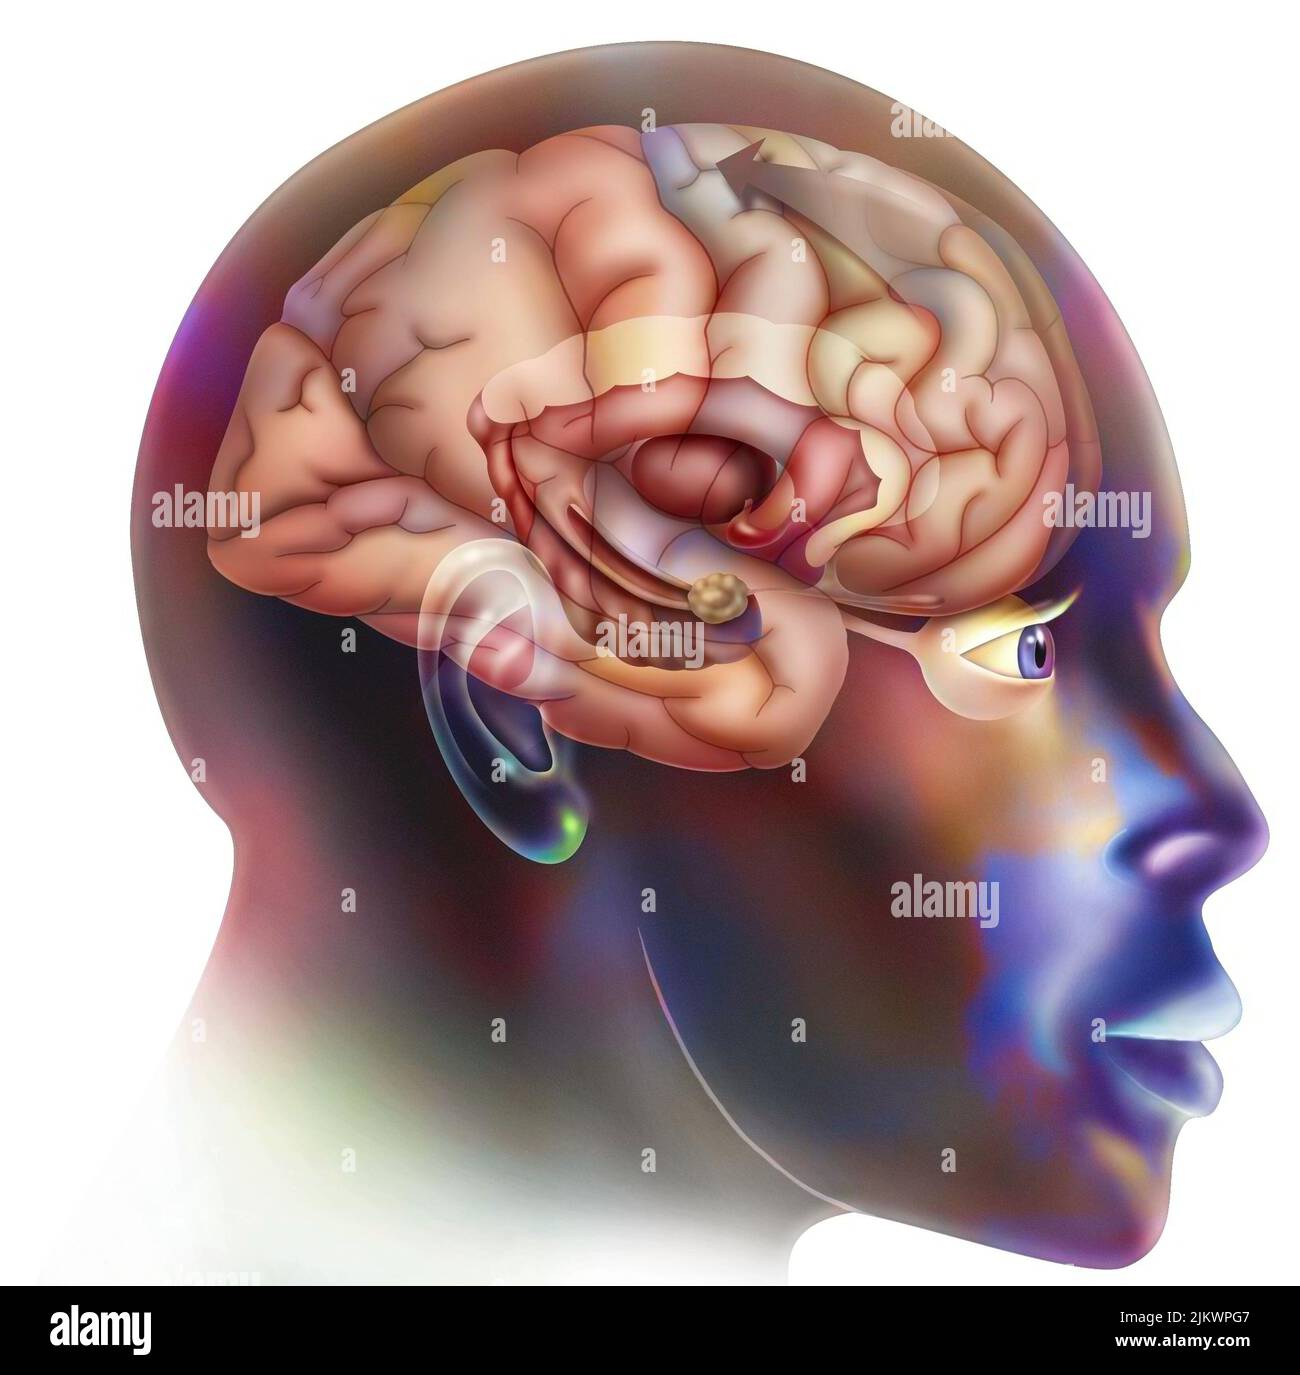

RF2JKWPG7–Troisième étape dans la façon dont le cerveau fonctionne quand vous tombez amoureux: La prise de décision.